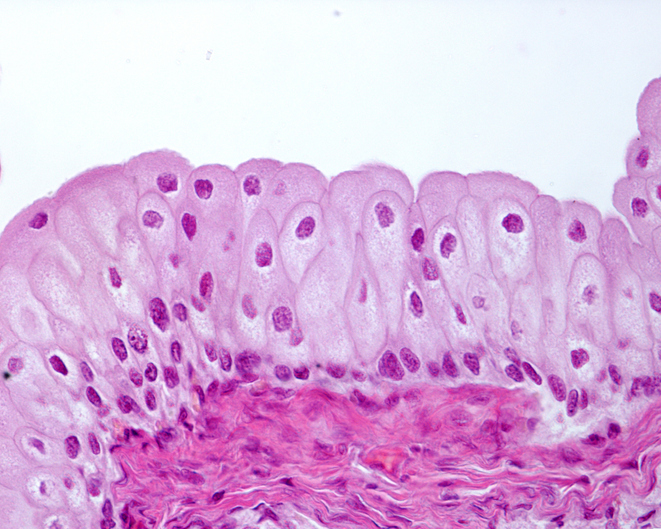

Este detalle es importante, porque para que una célula pueda utilizar su ADN, la cadena debe estar desempaquetada. Es decir, una célula solo puede expresar los genes que se encuentran en la eucromatina, sin embargo, los que están en la heterocromatina no llegan a leerse nunca por esa célula. Cada tipo celular mantiene desempaquetadas solo partes concretas del genoma, las que necesita para cumplir sus funciones, y el resto lo mantiene guardado.

Por eso, aunque todas las células del cuerpo tienen el mismo genoma, no todas expresan los mismos genes. Por ejemplo, las células epidérmicas, las del iris del ojo o las del folículo piloso expresan los genes responsables de la producción de melanina, el pigmento marrón que les confiere el color; sin embargo, las células del músculo cardíaco o las células nerviosas no expresan esos genes. O, por ejemplo, solo las células beta del páncreas pueden expresar el gen que produce la insulina, y si fallan, ninguna otra es capaz de cumplir esa función.